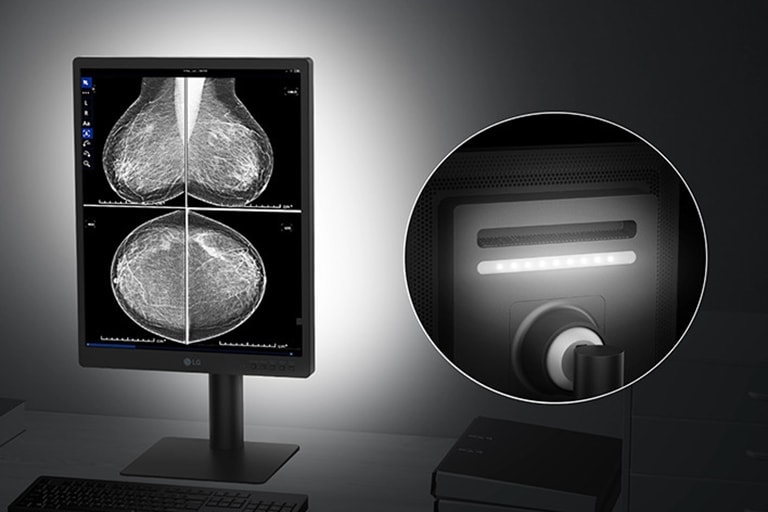

Down light & Wall light

Ideal diagnostic workspace

Down /Wall light mode enhances readability of documents below the monitor even in low-light environments.

*All images are shown for illustrative purposes only and may vary from the actual product/usage.